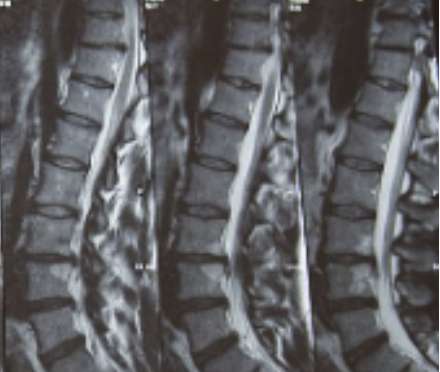

허리디스크를 정확하게 진단하기 위해서는 엑스레이로는 힘들며, MRI를 통해 검사해야 정확하게 볼 수 있습니다.

MRI가 몸에 좋지 않지만 허리 통증으로 엑스레이만 진행 할 경우 오진이 많아 지속적인 통증이 계속 된다면 허리디스크를 의심하고 MRI 검사를 한번 받아보시길 권유드립니다.